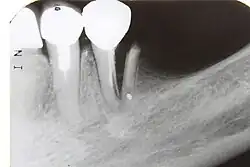

| Intrusão | •O dente é deslocado para o osso alveolar;

•Percussão dentária dará um som metálico (anquilótico) agudo. |

•Ausência de espaço do ligamento periodontal em parte ou na totalidade da raiz;

•A junção cemento-esmalte aparece mais apicalmente para o dente traumatizado. |

•Se formação de raiz incompleta:

–Dê tempo para o dente irromper naturalmente, mas se não houver movimento após algumas semanas, comece o reposicionamento ortodôntico intrusão> 7 mm: –Reposicionamento cirúrgico ou ortodôntico estabilizar com tala flexível por 4 semanas após o reposicionamento •Se a formação da raiz for completa: –Intrusão <3 mm: aguarde a erupção natural, mas se nenhum movimento após 2 a 4 semanas, reposicione cirurgicamente ou ortodonticamente Intrudido 3-7mm: reposicionamento cirúrgico ou ortodôntico intrusão> 7 mm: reposicionamento cirúrgico probabilidade de necrose pulpar nesses dentes, portanto, o tratamento endodôntico com obturação temporária de hidróxido de cálcio em primeira instância e iniciar tratamento endodôntico 2-3 semanas após o reposicionamento; •Estabilizar com contenção flexível por 4 semanas após o reposicionamento. |

•2 semanas: exame clínico e radiográfico.

•4 semanas: remoção da tala, exame clínico e radiográfico. •6–8 semanas: exame clínico e radiográfico. •6 meses: exame clínico e radiográfico. •1 ano: exame clínico e radiográfico. •Anualmente durante 5 anos: exame clínico e radiográfico. |